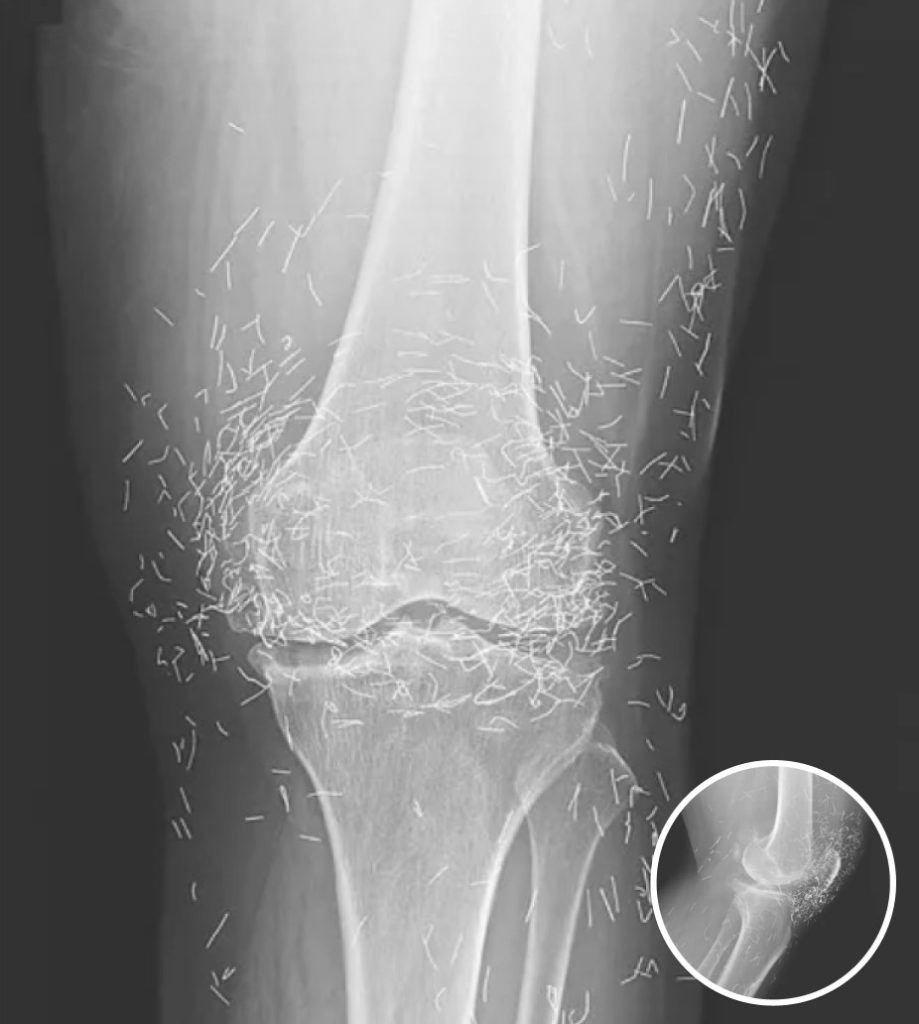

In a remarkable twist during a routine medical examination, doctors uncovered an unexpected surprise in the knees of a 65-year-old South Korean woman. While assessing her severe joint pain, X-ray imaging revealed the presence of hundreds of tiny gold needles embedded deep within her knee tissue. This startling discovery has raised numerous questions regarding the practice of acupuncture, particularly the implications of retaining needles within the body as part of treatment for chronic conditions. Such revelations compel both patients and practitioners to reconsider the safety and efficacy of alternative therapies commonly employed in managing pain.

Moreover, embedded needles can complicate medical imaging. Dr. Guermazi pointed out that they can obscure anatomical details during X-rays and may pose significant risks during MRI scans. The powerful magnetic fields employed in MRIs could cause the needles to shift, potentially leading to severe injuries, such as punctured blood vessels or other critical damage. These risks underscore the necessity for patients to be well-informed about the methods and implications of any alternative treatments they consider. It is vital for individuals to discuss with their healthcare providers any past or current alternative therapies, especially those involving the implantation of materials, to avoid unexpected complications during future medical assessments.